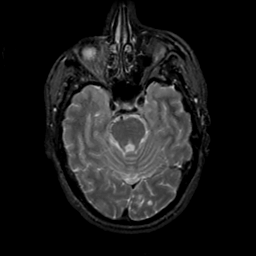

MR Study #19, August 25, 1991 -- Slice #16

[Home][Help][Clinical][Tour 1][Tour 2] Slice 16